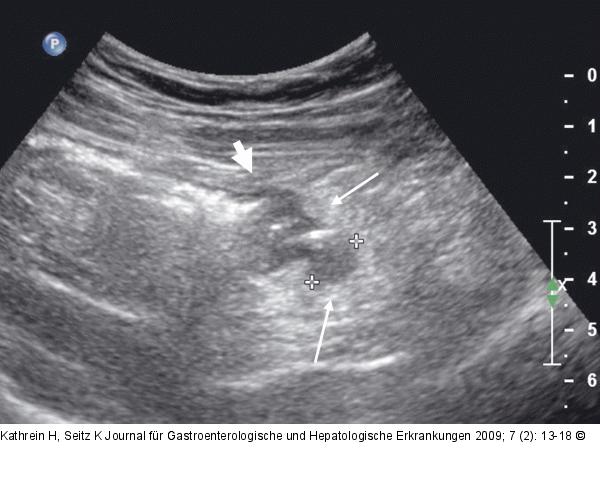

Abbildung 2: Divertikulitis Zweiter Schub einer Divertikulitis: Im druckschmerzhaften Bereich im linken Unterbauch 11 mm großes echoarmes Divertikel, außen am Colon descendens hängend (zwischen den +); gut erkennbare echoreiche Entzündungsreaktion (dünne Pfeile), Übergang aus der normal dicken Kolonwand in den verdickten Bereich (dicker Pfeil). |

Abbildung 2: Divertikulitis

Zweiter Schub einer Divertikulitis: Im druckschmerzhaften Bereich im linken Unterbauch 11 mm großes echoarmes Divertikel, außen am Colon descendens hängend (zwischen den +); gut erkennbare echoreiche Entzündungsreaktion (dünne Pfeile), Übergang aus der normal dicken Kolonwand in den verdickten Bereich (dicker Pfeil). |